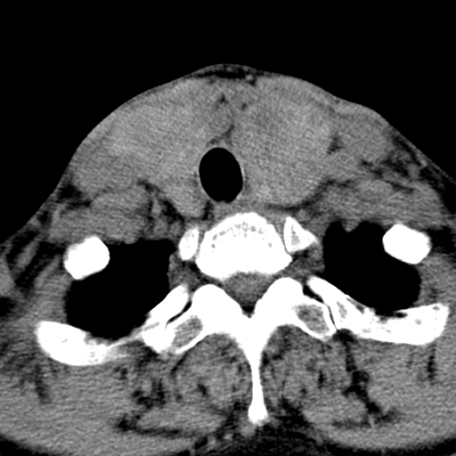

标题: CT24010:患者女56岁双侧甲状腺摘除术后一月复查,患者现感 [打印本页]

标题: CT24010:患者女56岁双侧甲状腺摘除术后一月复查,患者现感

“甲状腺摘除术后一月复查”,有病理吗?考虑术后复发,可能是恶性,颌下及左侧颈部淋巴结有肿大。

考虑术后复发,并颈部淋巴结肿大。请结合临床。

双侧甲状腺肿大,伴多发低密度灶(性质待定);建议行进一步检查。

双侧甲状腺肿大,周围结构不清,术后复发时间有点短,考虑出血并感染。